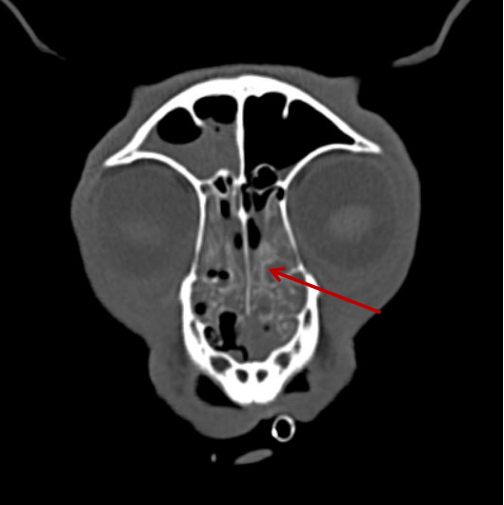

▲相比之下,這只狗狗的鼻竇炎可算是小毛病了。